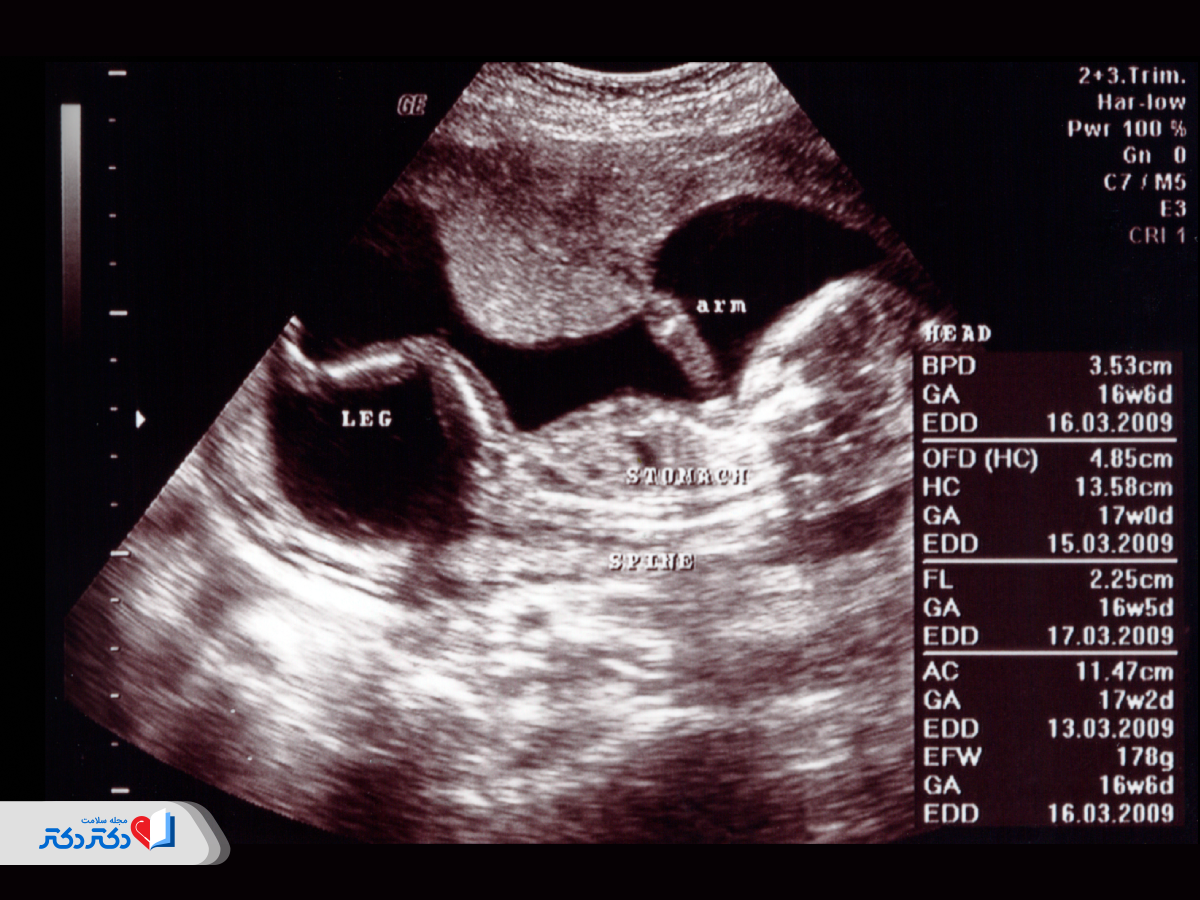

معنی اصطلاحات سونوگرافی آنومالی و تفسیر آن

مفهوم اصطلاحات سونوگرافی آنومالی که در گزارش نهایی ثبت میشوند بههمراه تفسیر آنها در ادامه آمده است:

| اصطلاحات | مفهوم | تفسیر |

| BPD (Biparietal Diameter) | قطر دوپاریتال یا قطر سر (فاصله بین دو طرف سر) |

| HC (Head Circumference) | دور سر |

| AC (Abdominal Circumference) | دور شکم |

| FL (Femur Length) | طول استخوان ران |

| CRL (Crown-Rump Length) | طول فرق سر تا کفل (طول از بالای سر تا پایین) |

| HL (Humeral length) | طول استخوان بازو |

| TCD (Trans-Cerebellar Diameter) | قطر مخچهای (قطر بین نیمکرههای مخچه) |

| FP (Fetal Pyelectasis) | پیلکتازی جنینی (قطر لگنچه کلیه) |

| IOD (Interocular Distance) | فاصله بینچشمی (اندازهگیری ناحیه بین دو گوشه داخلی هر دو چشم) | شناسایی سندرمها و ناهنجاریهای مادرزادی |

| OFD (Occipital-Frontal Diameter) | قطر پسسری-پیشانی (ناحیه بین پیشانی جنین و پشت سر) | کمک به پیشبینی شکل سر |

| BOD (Binocular Distance) | فاصله دوچشمی (اندازهگیری ناحیه بین دو گوشه خارجی چشمها) | شناسایی ناهنجاریها |

| EFW (EFW) | وزن تخمینی جنین |

اعداد نرمال در سونوگرافی آنومالی

پارامترهای مختلفی در اسکن آنومالی اندازهگیری میشوند که میانگین و محدوده اعداد نرمال آن به شرح زیر هستند:

| پارامترها | مقدار میانگین در هفته بیستم (میلیمتر) | محدوده نرمال (میلیمتر) |

| BPD | ۵۰ | ۴۷ تا ۵۳ |

| FL | ۳۳ | ۳۰ تا ۳۶ |

| HC | ۱۸۵ | ۱۷۰ تا ۲۰۰ |

| AC | ۱۵۵ | ۱۴۰ تا ۱۷۰ |

جدول زیر پارامترهای اصلی سونوگرافی آنومالی را بین هفتههای ۱۸ تا ۲۲ با حداقل اعداد نرمال مقایسه میکند:

| هفته بارداری | BPD (میلیمتر) | FL (میلیمتر) | HC (میلیمتر) | AC (میلیمتر) |

| هفته ۱۸ | ۳۸ | ۲۳ | ۱۳۲ | ۱۲۵ |

| هفته ۲۰ | ۴۹ | ۳۴ | ۱۷۰ | ۱۵۲ |

| هفته ۲۲ | ۵۷ | ۴۲ | ۲۰۸ | ۱۹۶ |

دادههای جدول بالا، حداقل اعداد اندازهگیری شده هستند؛ بنابراین مقدار میانگین و اعداد نرمال در سونوگرافی آنومالی دختر و پسر ممکن است چند میلیمتر کمتر یا بیشتر باشد.